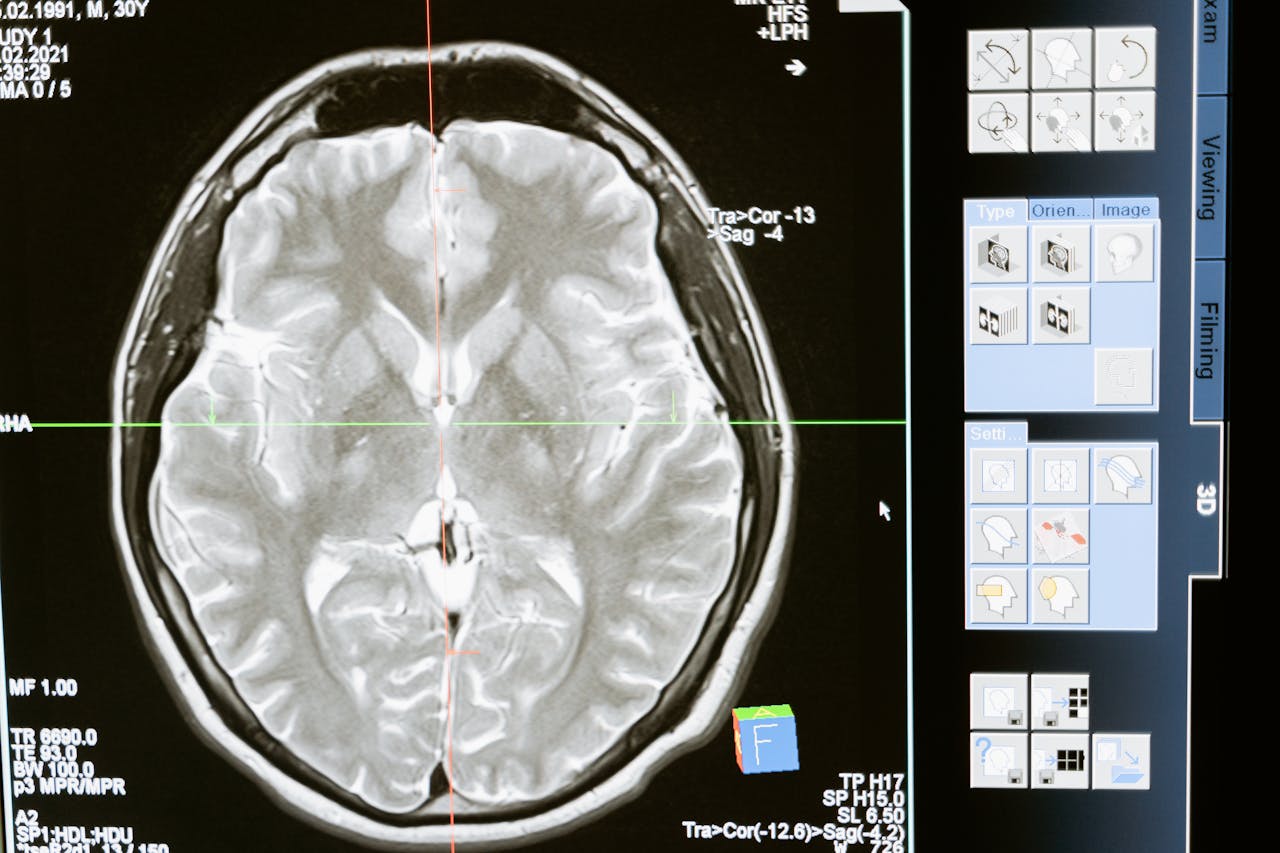

I trattamenti neurologici proposti dal Dr. Attilio Conte sono pensati per gestire diverse condizioni, dalle più comuni alle più complesse. Dopo una valutazione approfondita, viene definito un piano terapeutico personalizzato che può includere terapia farmacologica, monitoraggio clinico e indicazioni pratiche per la gestione quotidiana dei sintomi. Particolare attenzione viene data a disturbi come emicrania, tremori, neuropatie e deficit cognitivi. L’obiettivo è ridurre i sintomi e migliorare la funzionalità, con un percorso costruito su misura.

La visita specialistica neurologica rappresenta il primo passo per comprendere l’origine di disturbi come vertigini, perdita di memoria, formicolii o difficoltà motorie. Durante la visita, il Dr. Attilio Conte raccoglie informazioni dettagliate, esegue un esame neurologico completo e, se necessario, consiglia ulteriori approfondimenti diagnostici. Questo approccio permette di arrivare a una diagnosi chiara e di impostare un percorso terapeutico efficace. La visita è strutturata per essere chiara, approfondita e orientata alla soluzione.